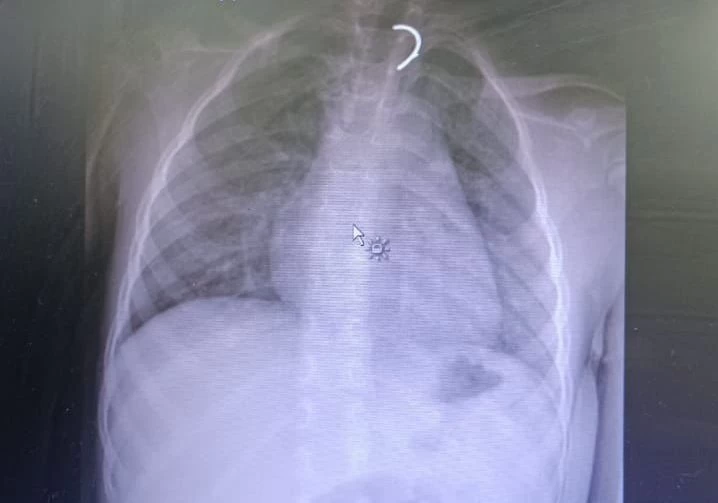

وقال إنه من خلال الكشف السريري تم العثور على قطعة (حلق) في بلعوم الطفلة، وبعد إجراء تصوير مقطعي للرقبة والصدر تبيّن وجود جسم غريب غير متجانس داخل الثلث العلوي من المريء بقياس 4 × 2 سم، تتوافق مع الفقرات T1 وT2، مما يشير إلى انحشار الجسم الغريب ليتم بعدها مباشرة تحويل الطفلة إلى غرفة العمليات.